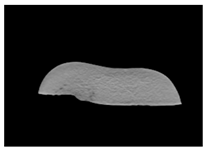

2. Materials and Methods

3. Results